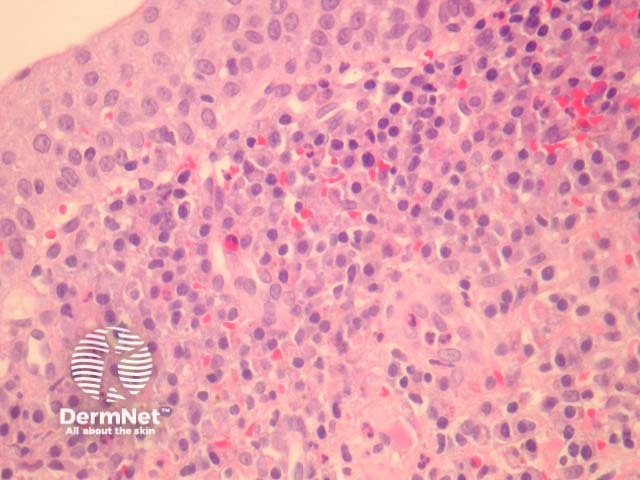

In Zoon balanitis/vulvitis, sections show mucosa which may be attenuated or eroded overlying a dense stromal infiltrate (figures 1,2). The infiltrate contains numerous plasma cells which often form sheets. There may be fewer eosinophils and neutrophils. Vascular ectasia and extravasated erythrocytes are common (figures 1,2,3).

Figure 2